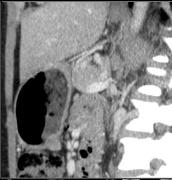

Image nodulaire isodense du

tumeur endocrine de la paroi posterieure de l'estoma |

Image multi- nodulaire a isodense

du tumeur endocrine a la parois posterieure de

l'estoma . Image TDM en coupe sagitale . |